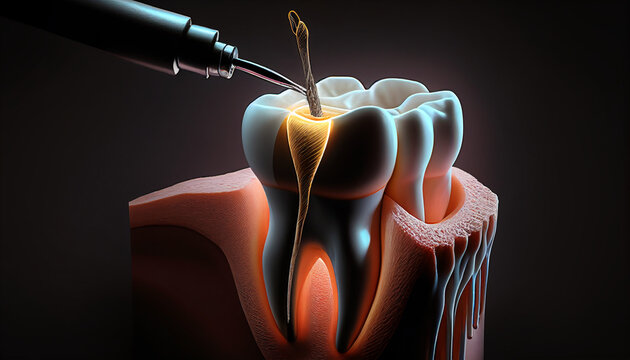

Root canal therapy removes infection from the tooth’s pulp, relieving pain, and saving the tooth from extraction or further damage.